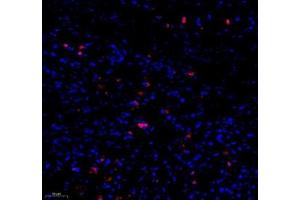

Caspase 3 抗体

(Caspase 3 (CASP3))

This gene encodes a protein which is a member of the cysteine-aspartic acid protease (caspase) family. Sequential activation of caspases plays a central role in the execution-phase of cell apoptosis. Caspases exist as inactive proenzymes which undergo proteolytic processing at conserved aspartic residues to produce two subunits, large and small, that dimerize to form the active enzyme. This protein cleaves and activates caspases 6, 7 and 9, and the protein itself is processed by caspases 8, 9 and 10. It is the predominant caspase involved in the cleavage of amyloid-beta 4A precursor protein, which is associated with neuronal death in Alzheimer's disease. Alternative splicing of this gene results in two transcript variants that encode the same protein. [provided by RefSeq, Jul 2008].